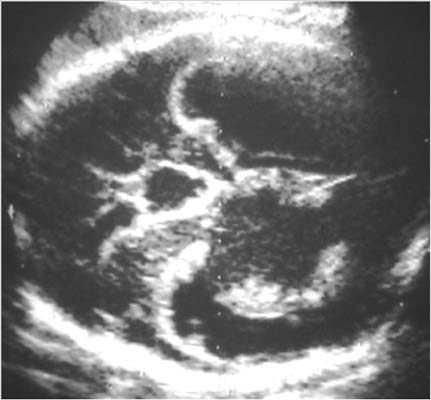

Glioblastome stade